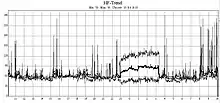

Older monitors used reel-to-reel tapes or C90 or C120 audio cassettes, moving at a 1.7 mm/s or 2 mm/s speed to record the data. The recording could be played back and analyzed at 60 times the recording speed, so 24 hours of recording could be analyzed in 24 minutes. Modern monitors record EDF-files on digital flash memory. The information is loaded on a computer, which counts ECG complexes; calculates summary statistics, such as average, minimum, and maximum heart rate; and finds parts of the recording that are worthy of further study.

After the recording of ECG signal for typically 24 hours, the signal must be analysed. A person would have to listen for the full 24 hours; instead integrated automatic analysis determines different sorts of heart beats, rhythms, etc. The success of the analysis is closely associated with the signal quality, which mainly depends upon the attachment of the electrodes to the patient's body. Incorrect attachment allows electromagnetic disturbance to add noise to the record, particularly with rapid patient movement, impeding processing. Other factors can also affect signal quality, such as muscle tremors, sampling rate and resolution of the digitized signal (high quality devices offer higher sampling frequency).

The automatic analysis commonly provides the physician with information about heart beat morphology, beat interval measurement, heart rate variability, rhythm overview and patient diary (moments when the patient pressed the patient button). Advanced systems also perform spectral analysis, ischemic burden evaluation, graph of patient's activity or PQ segment analysis. Also possible is the ability to monitor and analyse pacemaker impulse detection, useful for checking pacemaker function.